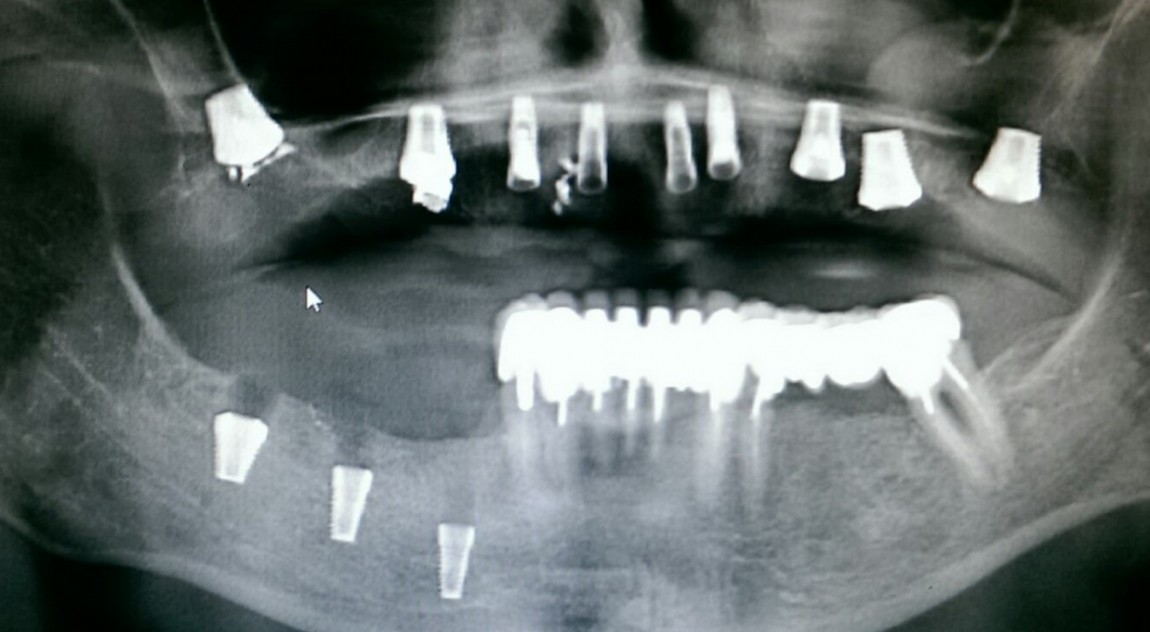

Цель имплантологического лечения - не воткнуть импланты так, чтобы они прижились, а создание надёжной и долговечной опоры под планируемую ортопедическую конструкцию.

В отличие от "отторжения", которое мы рассмотрели в прошлой статье, периимплантиты встречаются намного чаще. С счастью, они далеко не всегда приводят к утрате имплантатов и чаще обнаруживаются случайно при рентгенологическом обследовании...

В прошлой статье я рассказал вам о причинах о причинах возникновения и развития перимплантита. Сегодня публикую вторую часть статьи, в которой предлагаю обсудить методы профилактики и лечения периимплантита